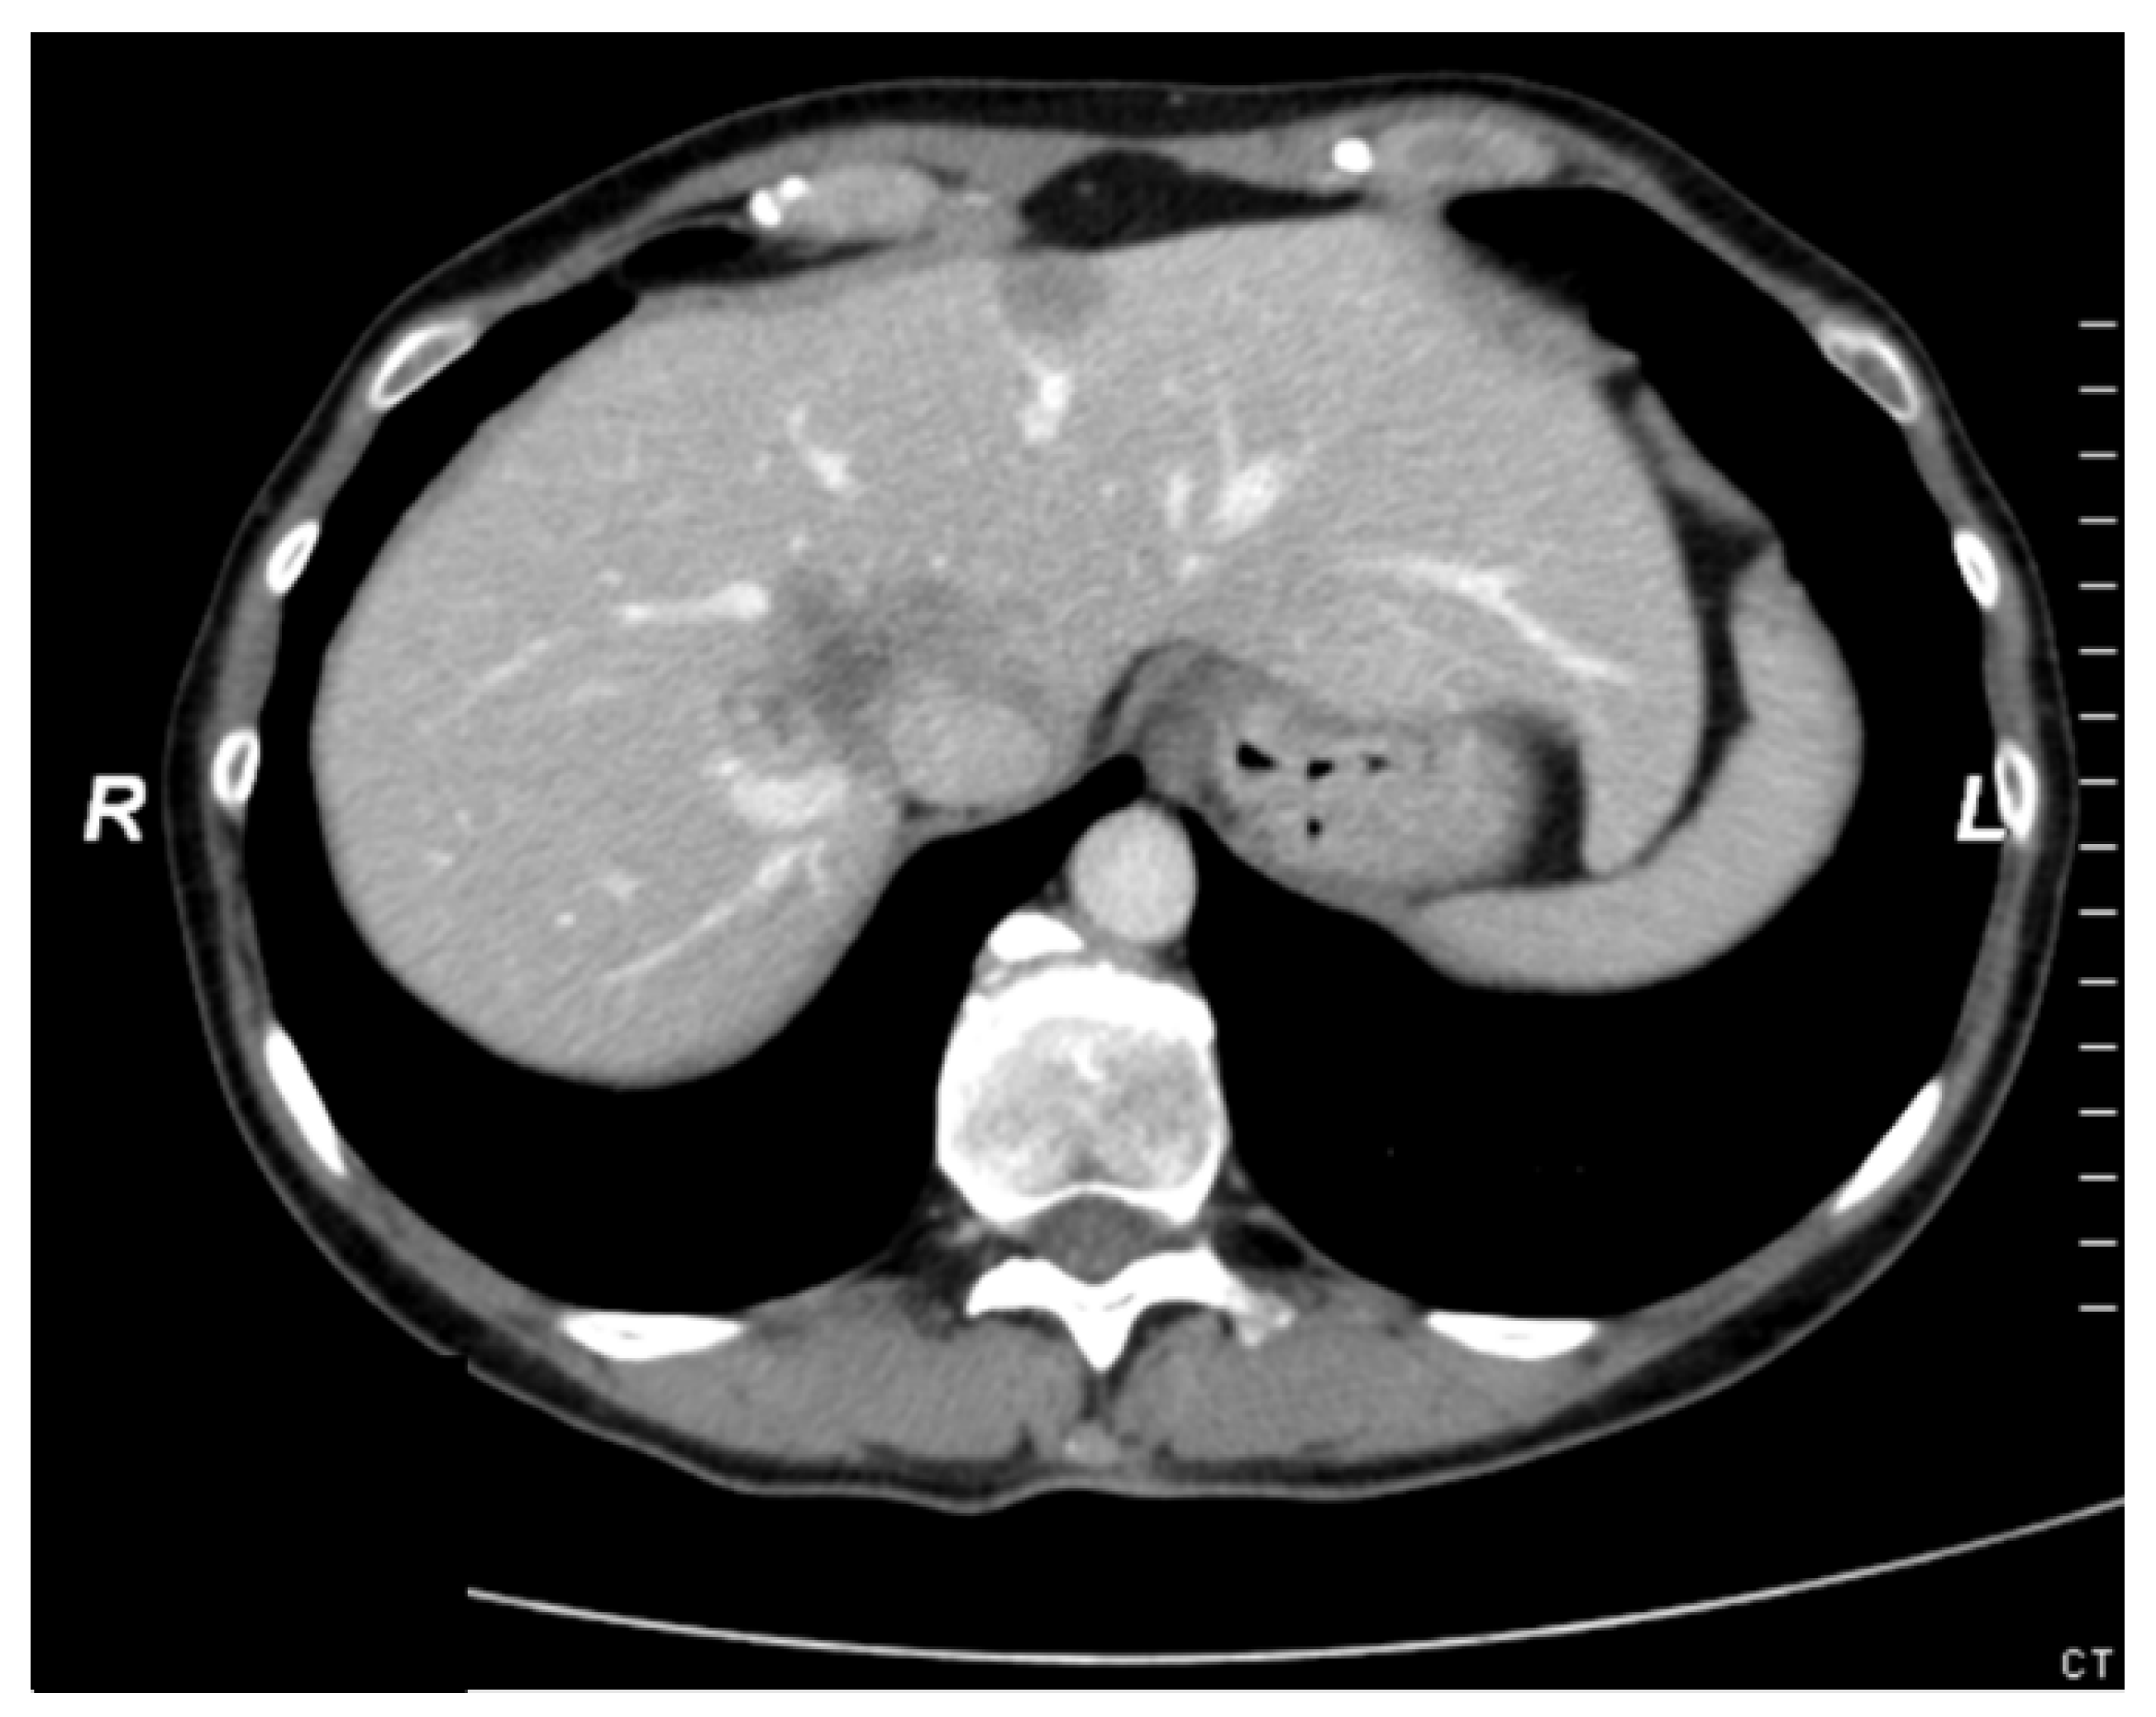

3.6. Case Report 1

3.7. Case Report 2